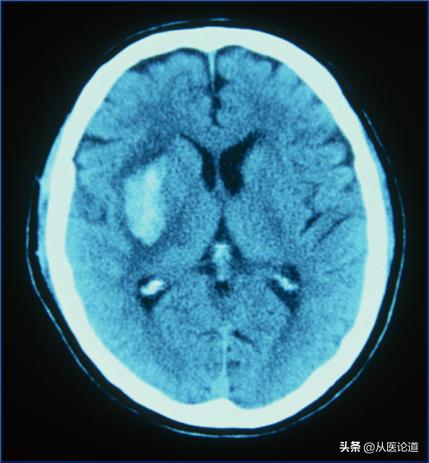

内脏出血:呕血、黑便、咯血、尿血、阴道出血、颅内出血危及生命。